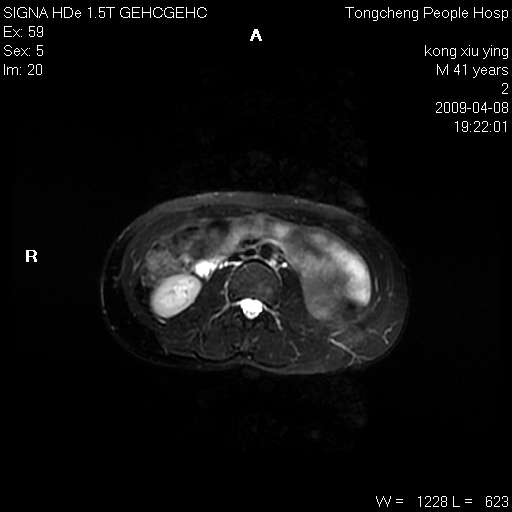

标题: CL1008:【经典】胆囊石榴籽样结石。 [打印本页]

标题: CL1008:【经典】胆囊石榴籽样结石。

女,41岁。健康体检——彩超提示:胆囊显示不清。平素健康,无不适感。

腹部mr扫描及mrcp,图像如下:

胆囊石榴籽样结石。